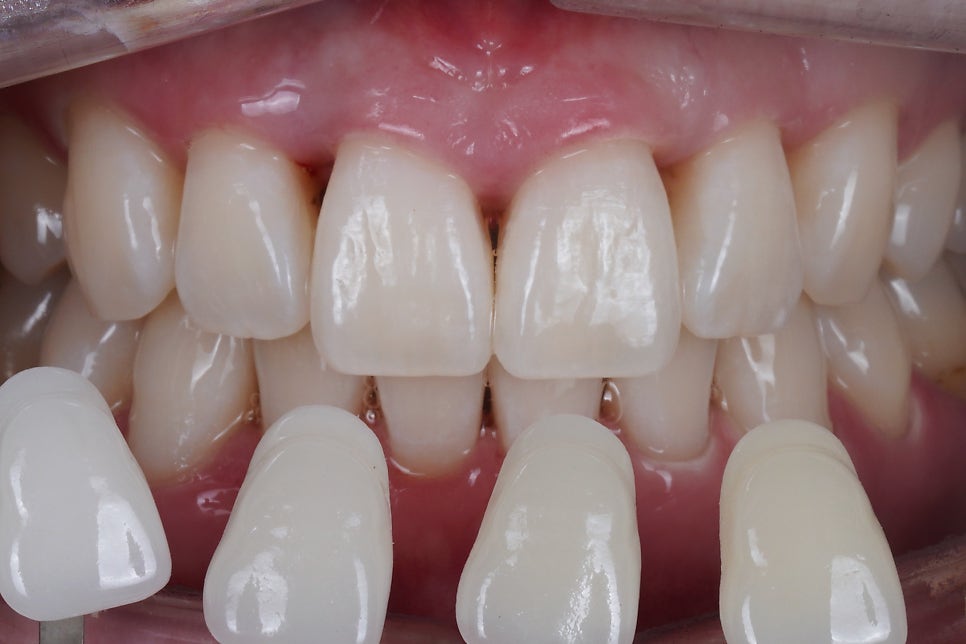

출처 아카이브 열기기존에 교정치료를 받으셨는데

블랙트라이앵글이 심해서

너무 신경쓰여 치료를 받으러 오셨어요.

잇몸뼈가 안좋으셔서

치아를 잡아주고 있는 잇몸이

내려가서 생긴 문제였습니다.

색상이나 모양을 맞추는 것 뿐만 아니라

장기적으로 얼마나 유지관리가 잘 되도록

치료하는지가

미용 치료에 있어 굉장히 중요한 부분입니다.

사례자분께서는 굉장히 만족하셨고요,

"너무 신기해요"

라고 3번이나 말씀해주셨어요.

전혀 티 나지 않게 잘 되었습니다.